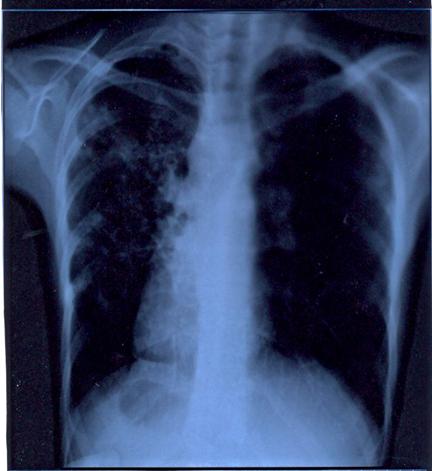

Examinarea unui singur esantion de sputa nu este in regula suficienta pentru identificarea bacililor tuberculosi in sputele paucibacilare sau intermitent pozitive. Pentru acest motiv in practica ftiziologica a devenit uzuala recoltarea repetata a sputei in 3 zile consecutive. Pentru imaginile radiologice aparent inactive sau de activitate dubioasa (leziuni nodulare, leziuni minime, leziuni sechelare) este indicata examinarea unui numar mai mare de esantioane de sputa (6-10) prin cultura.